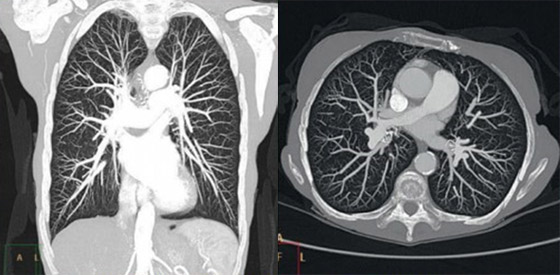

Шумы и артефакты на изображениях ограничивают возможности визуализации необходимых структур. Технология Philips IMR задает новое направление в развитии качества КТ-изображений, обеспечивая практически полное отсутствие шумов в изображениях и существенное улучшение качества изображений в сочетании с заметным снижением лучевой нагрузки1.

Итеративная модельная реконструкция отличается улучшением показателя низкоконтрастного разрешения, обеспечивая надежную диагностику схожих по плотности структур. Преимущества IMR особенно очевидны при диагностике онкологических и кардиологических заболеваний, а также педиатрии. Время реконструкции для большинства стандартных протоколов составляет не более 3 минут*.